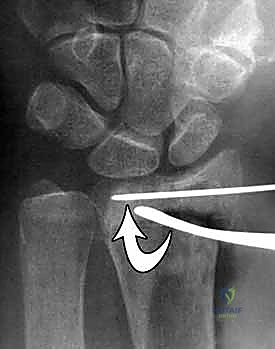

- تشوه في شكل الرسغ: يُعرف كلاسيكياً باسم "تشوه ظهر الشوكة" (Dinner fork deformity) إذا كان الكسر مزاحاً للخلف.

تُعرف كسور الكعبرة البعيدة بأنها تشمل منطقة الكردوس (Metaphysis)، وتحديداً المنطقة الواقعة ضمن طول السطح المفصلي الذي يعادل أوسع جزء من الرسغ بأكمله. في عياداتنا، نقوم بتقييم هذه الكسور بدقة متناهية بناءً على عدة خصائص رئيسية تحدد مسار العلاج:

- الموقع والاتجاه: هل يشمل الجانب الأمامي (الراحي - Volar) أم الخلفي (الظهري - Dorsal)؟

- امتداد الكسر: هل هو خارج المفصل (Extra-articular) أم داخل المفصل (Intra-articular)؟

- درجة التفتت: هل العظم مكسور إلى قطعتين أم مفتت إلى عدة شظايا؟